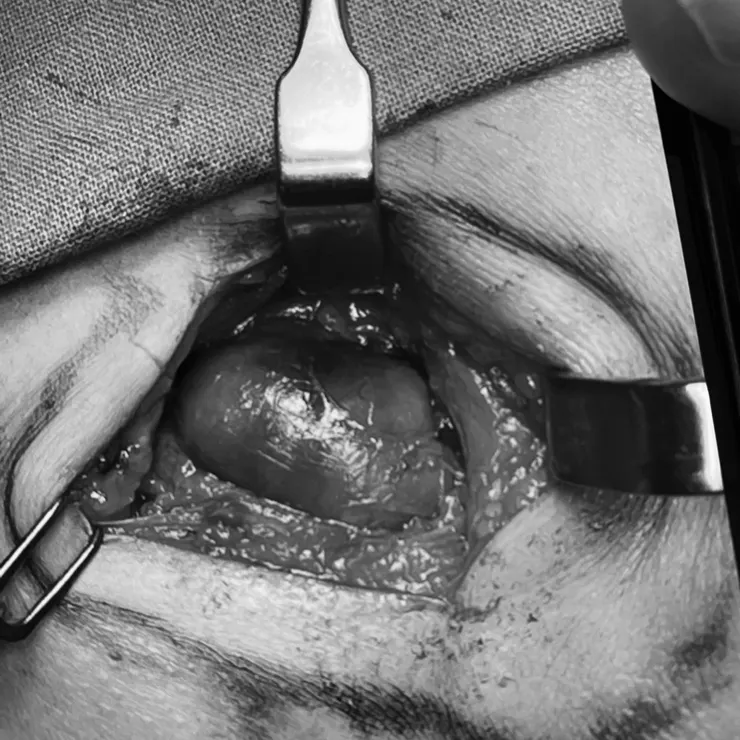

打開頸部看到的腫塊(用黑白圖比較不嚇人)

頸部切下來的腫塊(已部份引流)